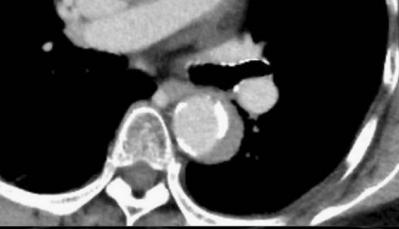

下图的胸部CT平扫,有什么致命的问题?

图7

仔细一看,主动脉里面有线样阴影!并且,线样阴影两边的密度一高一低!

图8

增强CT一看,主动脉夹层,密度相对高的是流动的血液!

图9